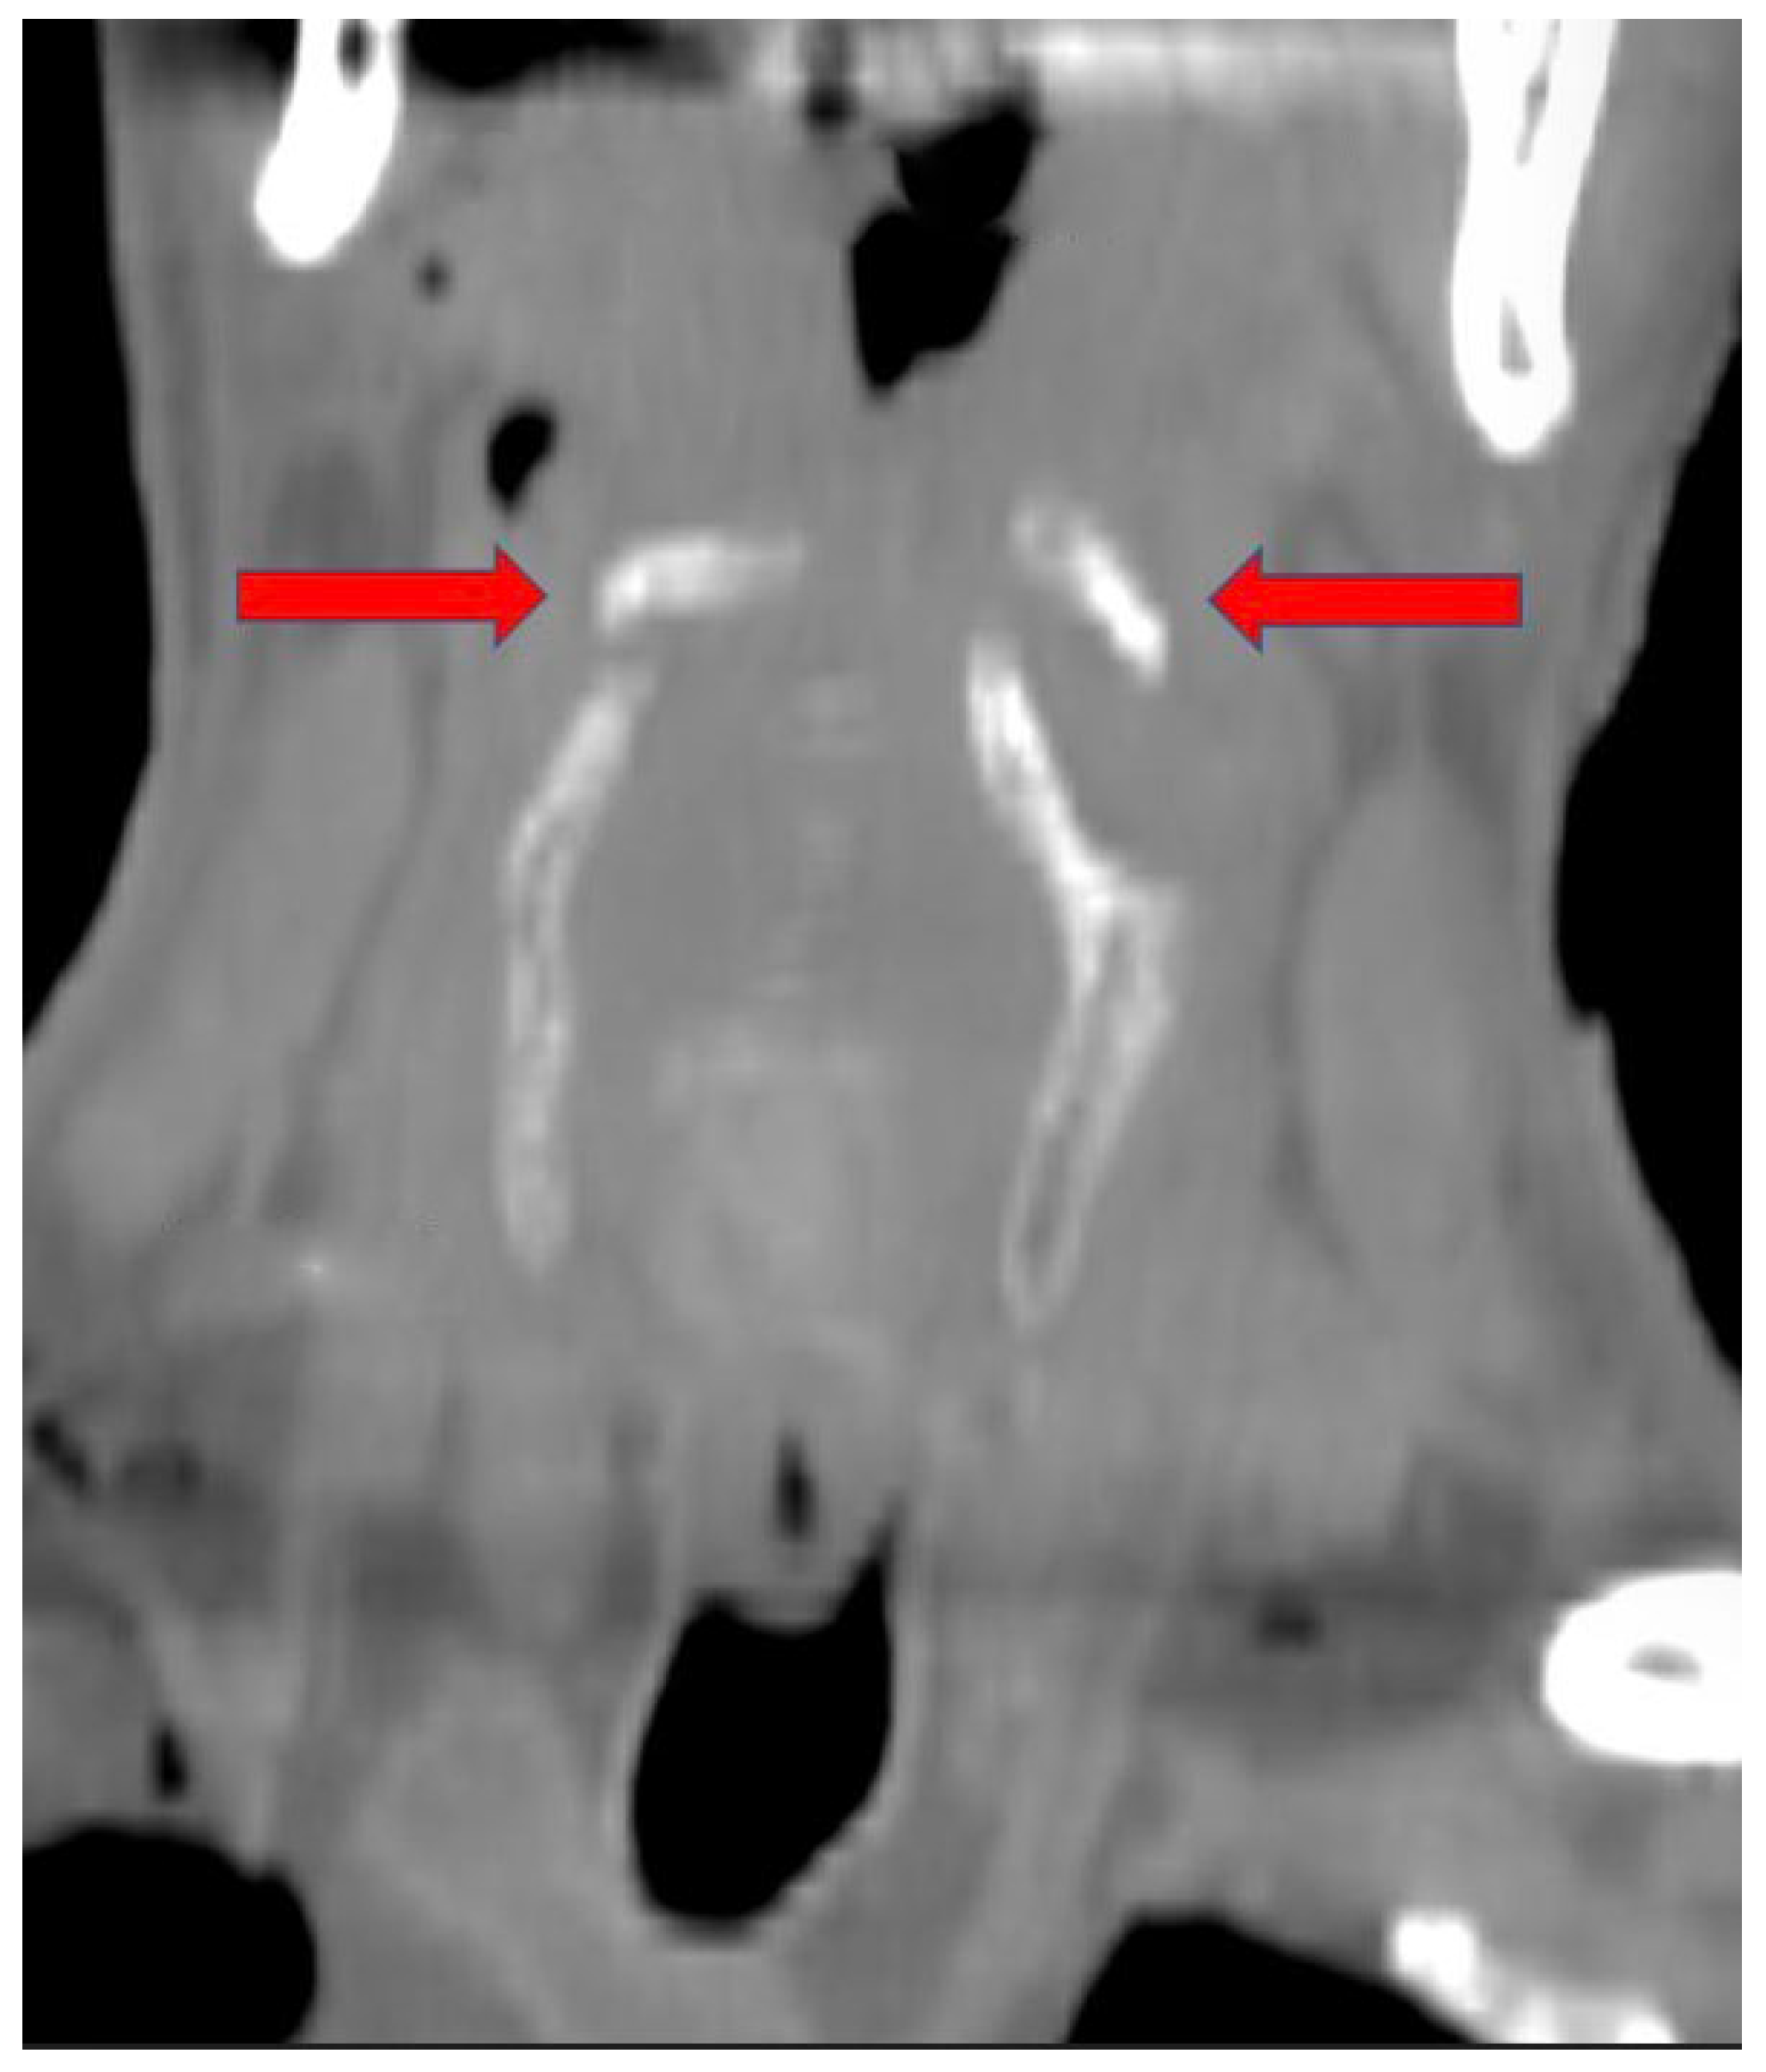

2. Case Report